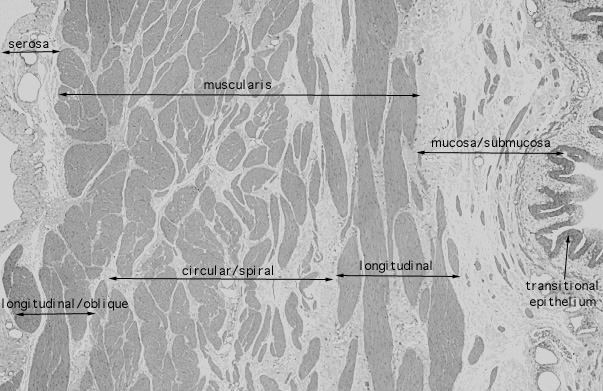

urinary bladder, relaxed

165. Urinary System urinary bladder, relaxed